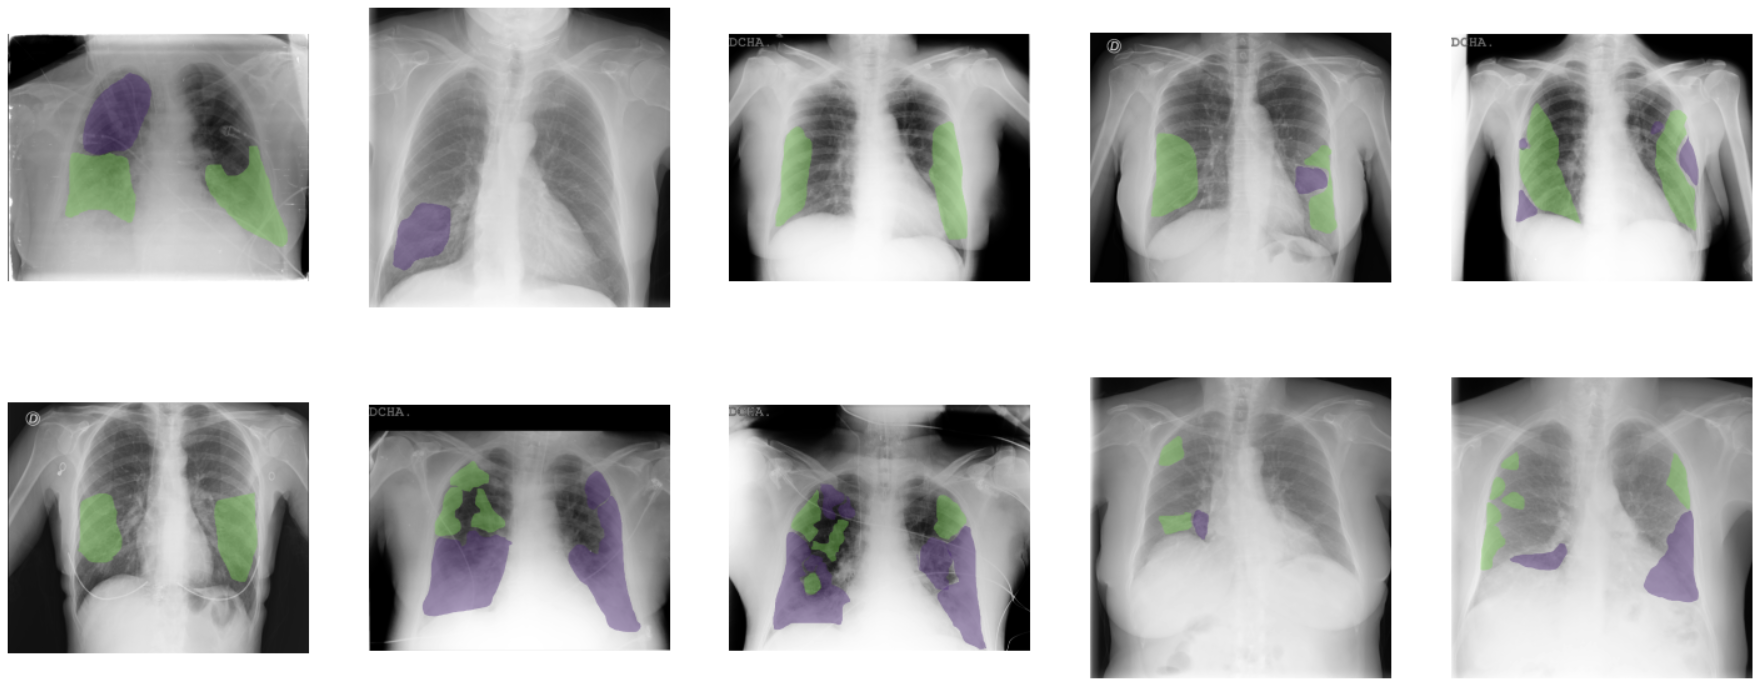

Annotation of regions of interest

Since some lesions such as infiltrates, ground glass opacities or consolidation patterns are the most frequent in COVID-19 patients, a sub-set of 10 images were annotated with their ROIs by a team of eight radiologists from the Hospital Universitario de San Juan de Alicante, for the first iteration of the BIMCV COVID-19+ dataset.

As it can be seen in Figure 3, ROIs corresponding to these findings were labeled at a pixel level using XNAT OHIF Viewer [25]. OHIF is a zero-footprint medical image viewer provided by the Open Health Imaging Foundation that stores an XML output with the ROI paths. This information of great value to train semantic segmentation networks, such as UNet [26], in order to extract characteristics such as the extension and exact location of the lesions. Table 4 shows the findings annotated at a ROI level.